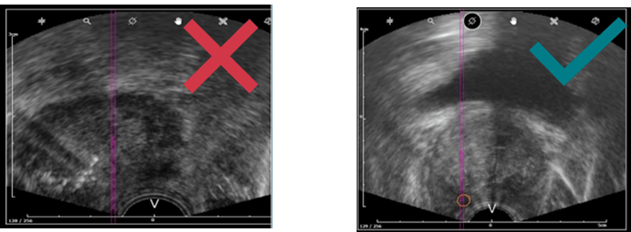

c. la profondeur des US n’est pas correctement ajustée

- Ajustez la profondeur de la prostate, c’est-à-dire que la prostate ne doit pas dépasser plus de la moitié de l’image ultrasons.

- Lorsque vous réalisez un panorama, assurez-vous que la prostate est contenue dans l’encadré jaune.